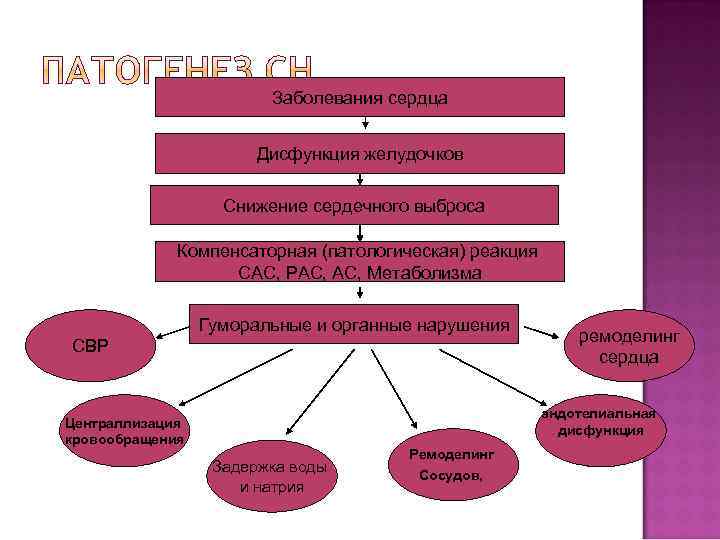

Тремя ключевыми событиями на пути развития ХСН становятся: заболевания сердечно-сосудистой системы; снижение сердечного выброса; задержка натрия и воды в организме.

Тремя ключевыми событиями на пути развития ХСН становятся: заболевания сердечно-сосудистой системы; снижение сердечного выброса; задержка натрия и воды в организме.

Заболевания сердца Дисфункция желудочков Снижение сердечного выброса Компенсаторная (патологическая) реакция САС, РАС, Метаболизма Гуморальные и органные нарушения СВР ремоделинг сердца эндотелиальная дисфункция Централлизация кровообращения Задержка воды и натрия Ремоделинг Сосудов,

Заболевания сердца Дисфункция желудочков Снижение сердечного выброса Компенсаторная (патологическая) реакция САС, РАС, Метаболизма Гуморальные и органные нарушения СВР ремоделинг сердца эндотелиальная дисфункция Централлизация кровообращения Задержка воды и натрия Ремоделинг Сосудов,